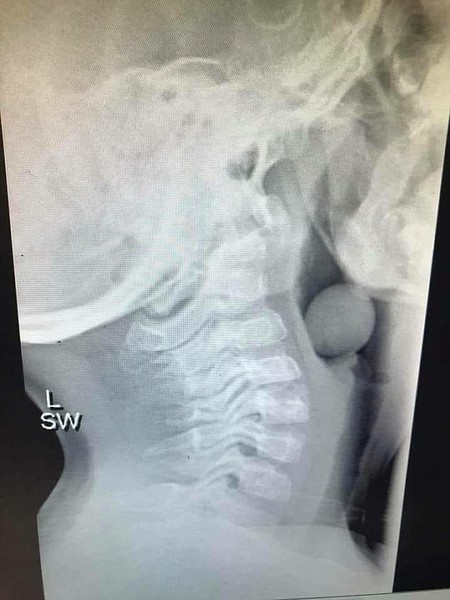

Su nombre es Angela Henderson y hace unos días compartió la radiografía de su hijo de 5 años después de atragantarse con una uva que podría haber acabado con su vida de haber taponado completamente la entrada de la laringe.

Según leemos en DailyMail, al pequeño de 5 años lo tuvieron que tratar con anestesia general para poder trabajar sobre su interior de manera segura y sin riesgos añadidos. Si la uva se hubiera movilizado hacia la tráquea no habría podido respirar, y el riesgo de muerte habría sido evidente.